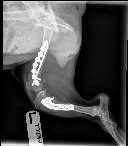

At our vet, it was determined that Krissie’s injuries were far worse – a whole lot worse. Her left leg was broken in two places, her right leg was fractured and she had four pelvic factures. She probably was hit by a car and miraculously survived. Our vet was concerned that she would need some surgery on pelvic fractures and would probably lose her left leg but wanted us to take her to the local specialist. Through all this and to the amazement of all, Krissie was still walking and never complained. No whimpering, no snarling, no yelping, no nothing. All she ever did was wag her tail and was happy to meet all that came her way. She is quite the trooper.

At the specialist, it was good news. Her right leg fracture and pelvic fractures were healing on their own and it was best to just let them be. Her left leg could be saved with the help of plates and screws. Her surgery was scheduled that afternoon and the following morning came home to begin the long recovery process.